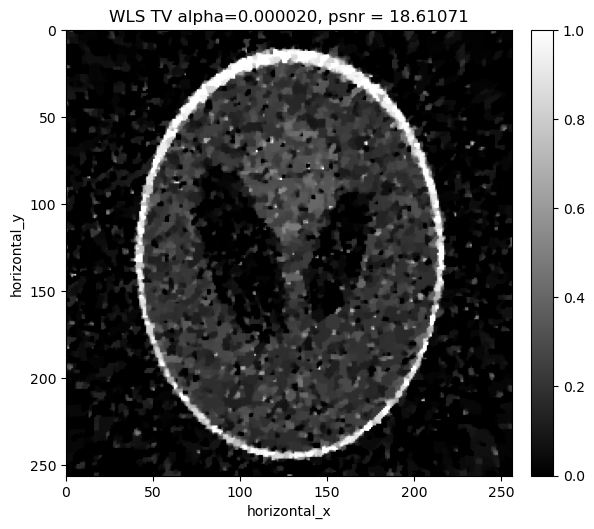

[22]:

show2D([recon_ls_tv], ["LS TV alpha=%7.6f, psnr = %7.5f" % (alpha,psnr_ls_tv_alpha[i])], cmap=cmap,fix_range=(0,1), size=(10,10), origin='upper-left')

../../_images/demos_LS_WLS_KL_TotalVariation_34_0.png

alpha=0.000020, psnr= 17.222